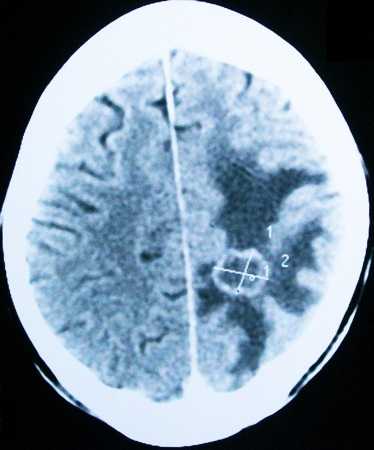

На снимке отек мозга:

Вследствие гематомы: а. На КТ; Б. На МРТ.

Из-за накопления жидкости в тканях мозга, происходит давление внутри, возникает отек.